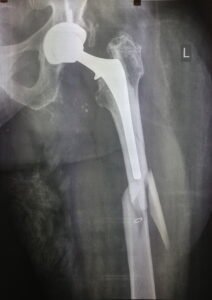

- Περιπροθετικό κάταγμα στην περιοχή του ισχίου στο επίπεδο του εμφυτεύματος.

- εσωτερική οστεοσύνθεση με πλάκα και αρκετή ελαστικότητα στο σύστημα.

- Ο ασθενής είναι σε πλήρη δραστηριότητα σε διάστημα δυόμισι μηνών μετά το κάταγμα.